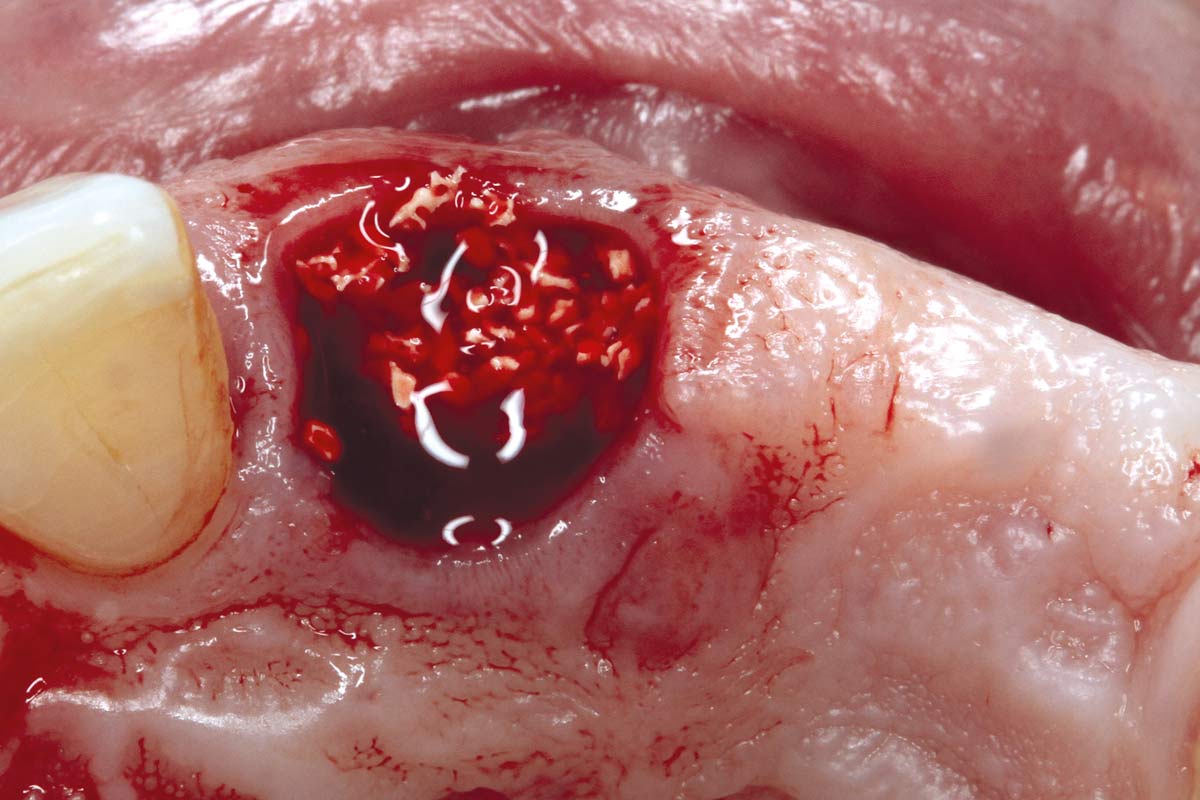

07/17 - cerabone® mixed with Straumann® Emdogain® applied to the extraction socket.

Socket preservation using cerabone® and Straumann® Emdogain® - Dr. S. Pelekanos